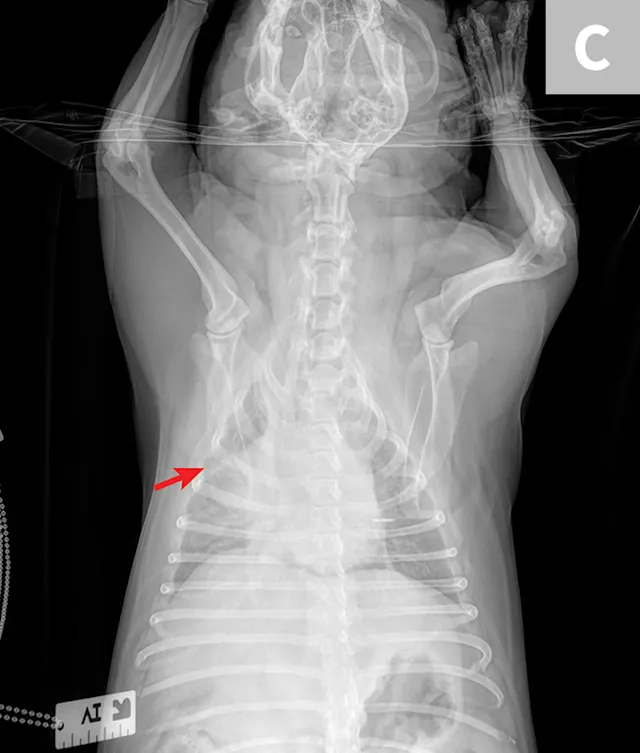

Thoracic radiographs (Figure) show an alveolar lung pattern in the ventral aspect of the right middle lung lobe that is most consistent with aspiration pneumonia or bronchopneumonia. Hemorrhage, neoplasia, and bronchial obstruction are also on the differential list but are considered less likely. Hepatomegaly is present, as is radiographic evidence of possible palate/pharyngeal region swelling and aerophagia.

FIGURE Right lateral (A), left lateral (B), and ventrodorsal (C) thoracic radiographs of the patient. Palate/pharyngeal region swelling can be observed (Barrow), as can an alveolar lung pattern in the ventral aspect of the right middle lung lobe (Carrow), which is most consistent with aspiration pneumonia or bronchopneumonia.